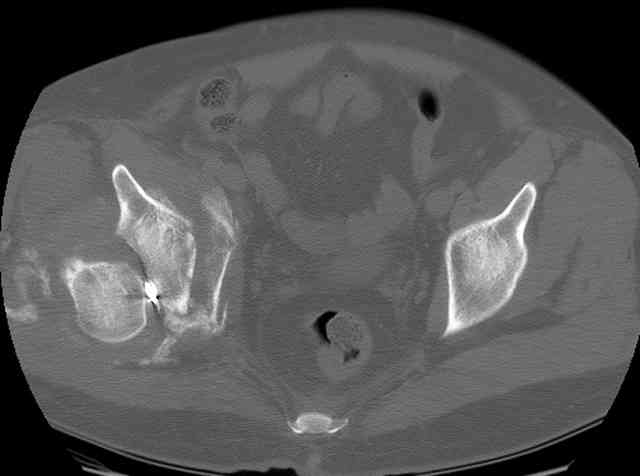

The unstable caudal segment is secured by the lower 2 plate screws and the AC medullary screw... always assure that your fixation is sufficient to defeat the instability... part of your prop plan... but assure it before you close... it¹s your last chance... you shouldn't have to be pushing on the hip in contorted ways to determine your fixation stability...you can if that makes you 'comfortable'.

A CT scan will rarely lie to you...reveals your reduction and implants...we use it to assess, teach, grade, and try to get better next time.

For Alex... here are some cannulated and 7mm screws for you... notice the fracture malreduction as indicated by the head subluxation on both views...this was a percutaneous technique without open reduction... I don¹t like it but there it is... the fixation technique is not at fault, because there was no open reduction of the fracture... but let¹s not get in to all that.